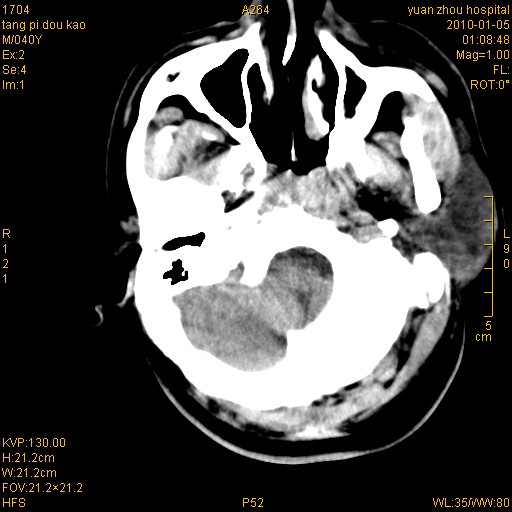

标题: CT23986:M 40Y 外伤数小时 [打印本页]

标题: CT23986:M 40Y 外伤数小时

右额叶脑挫伤,脑内血肿形成。左顶枕硬膜外血肿。

1)左侧颞枕部硬膜外血肿。2)右侧额部硬膜下血肿。3)双侧额叶及右侧基底节下部脑挫裂伤。4)蛛网膜下腔出血。5)脑水肿。6)左侧前组筛窦及左侧额窦炎症。

右额叶脑挫伤,脑内血肿形成。左颞枕硬膜外血肿。蛛网膜下腔出血。